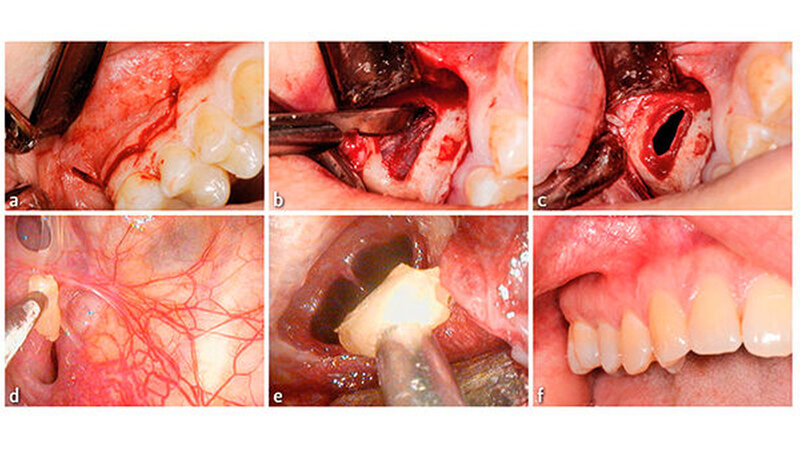

Nach ausführlicher Besprechung der Therapieoptionen mit der Patientin und der Aufklärung über mögliche Komplikation wurde eine chirurgische Entfernung des Wurzelrests vereinbart. Der Eingriff erfolgte nach präoperativer Gabe von Dalacin 300 mg 1 h präoperativ und über drei Tage postoperativ (anamnestisch berichtete die Patientin über eine frühere Amoxicillin-Unverträglichkeit) ambulant. Der Eingriff erfolgte in Lokalanästhesie mittels Septanest 1 : 200000. Der operative Zugang erfolgte mittels eines girlandenförmigen Paramarginalschnitts ca. 3 mm unterhalb des Sulcus innerhalb der Attached Gingiva mit mesialer und distaler Entlastung in regio 14–16.

Nach Abschieben des Mukoperiostlappens wurde der Knochen bis zur Schneider’schen Membran mittels Piezosurgery abgetragen. Es erfolgte ein Horizontalschnitt durch die Membran und damit die Eröffnung des Sinus maxillaris. Mittels eines flexiblen Endoskop konnte der Wurzelrest in regio des Ostium naturale visualisiert und mittels eines feinen Saugers adhäsiv aus der Kieferhöhle entfernt werden.

Die Kieferhöhle wurde mehrfach mit NaClLösung gespült und endoskopisch kontrolliert. Die Schneider’sche Membran wurde mit resorbierbaren Nähten 5.0 verschlossen und die Gingiva mit nicht resorbierbaren Einzelknopfnähten geschlossen (5.0 und 6.0). Postoperativ wurden Analgetika (Dafalgan 500 mg 111 für 3 d, Brufen 600 mg bei Bedarf), ein Antibiotikum (Dalacin C 300 mg 111 für 3 d) gegeben und eine Mundspüllösung rezeptiert (Chlorhexamed® FORTE 0,2 Prozent, täglich 2× den Mund für 1 min spülen). Um die Belüftung der Kieferhöhle zu gewährleisten, wurde ein Nasenspray abgegeben.

Außerdem wurde die Patientin darauf hingewiesen, wenn möglich nicht zu niesen oder zu schnäuzen (falls dies trotzdem erfolgt: ohne zugehaltene Nase oder zugehaltenen Mund) und für die nächsten fünf Tage auf sportliche Aktivitäten oder starken Wärmeeinfluss zu verzichten (Abb. 3).